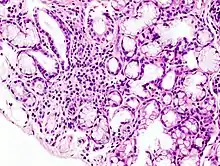

Image with a microscope of focal lymphoid infiltration in the minor salivary gland associated with Sjögren's syndrome. | |